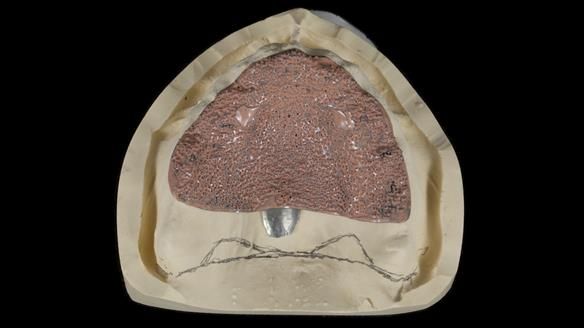

We provided her with an immediate upper denture (Mk 1), followed by a definitive metal-based upper denture (Mk 2). A lower removable partial denture was discussed, to be made only if needed once the upper treatment was complete. However, at review, this wasn’t necessary — Adnana had excellent neuromuscular control and function, even with a shortened dental arch (SDA).

Rowan, Sam Hesketh and Chris Hesketh provided the stunning technical work. I am very lucky to have them.